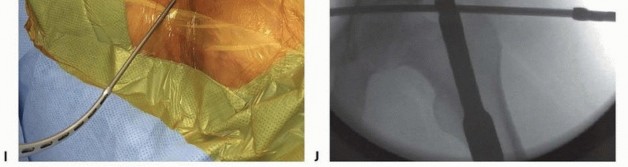

A unicortical drill hole, no more than 1 to 2 cm deep, initiates access within the crest. Pin direction is judged by manually grasping the crest within the surgeon's digits as described. This is typically 25 to 45 degrees medially and 10 to 15 degrees caudally. The pin may be introduced through the established surgical wound or adjacent (medial) percutaneous ones ( TECH FIG 2I). The pin is advanced 5 cm (50-mm threaded, 5.0-mm diameter pin), directed within the pillar between the osseous tables of the ilium. The second pin and the third, if applicable, are inserted one fingerbreadth posterior to the previous pin. The narrow and curved profile of the crest does not allow parallel pin insertion and, on occasion, accommodates no more than two pins. 316

F. Palpation of the inner and outer tables confirms proper pin trajectory. G. The rule of thirds (cross-sectional junction of inner third and outer two-thirds of the crest) aids in establishing the preferential pin entry point. H. This facilitates pin insertion, preventing misdirection and premature exit. I. Alternatively, pins may be placed through percutaneous wounds subjacent to the open surgical incision. J. Pins should converge on the supra-acetabular region while remaining within the anterior pillar. K. Fluoroscopic guidance facilitates proper pin placement within the inner and outer tables. (A: Modified from Yang AP, Iannacone WM. External fixation for pelvic ring disruptions. Orthop Clin North Am 1997;28:331-344; J: Modified from Poka A, Libby E Indications and techniques for external fixation of the pelvis. Clin Orthop Relat Res 1996;329:54-59.)

Subsequent pins should appear to converge toward each other and the common target of the supraacetabular region within the anterior pillar ( TECH FIG 2J). In an effort to retain intrapelvic tamponade, pins may be introduced through a similar approach without elevation of periosseous muscular attachments. Small Kirschner wires or spinal needles are directed along the iliac fossa to orient proper pin placement. Inner and outer table soft tissue attachments are preserved. Hematoma is not accessed and intrapelvic tamponade is preserved. A fluoroscopic obturator oblique outlet view of the pelvis can aid in identification of misdirected pins exiting the desired intercortical path ( TECH FIG 2K). 1. ##